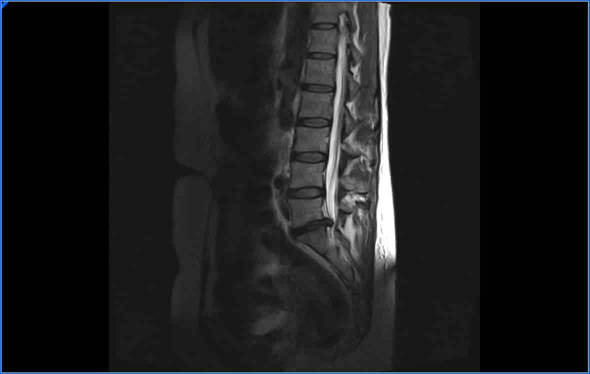

Tener dolor debido a una hernia discal es bastante habitual, se estima que el 80% de las personas van a tener problemas de espalda en algún momento de su vida. Cuando tenemos dolor provocado por una hernia discal lo normal es que en 8-12 semanas este desaparezca. El 90-95% de las hernias discales van evolucionar favorablemente con el tiempo.

Hay ocasiones en las que incluso las hernias discales llegan a desparecer, sobre todo cuando son estrusas y de gran tamaño. Una hernia estrusa es aquella que rompe el ligamento vertebral común posterior y se aloja dentro del canal lumbar.

Aunque parezca sorprendente así es, una hernia puede desaparecer, en ocasiones realizamos resonancia magnética de control y donde había una gran hernia discal ahora no hay nada.

El material discal al introducirse en el canal lumbar genera una reacción inflamatoria, las células inflamatorias producen unas sustancias llamadas enzimas que tienen la misión de degradar la hernia discal. El cuerpo considera a la hernia discal como un cuerpo extraño y va a tratar de “destruirla”.